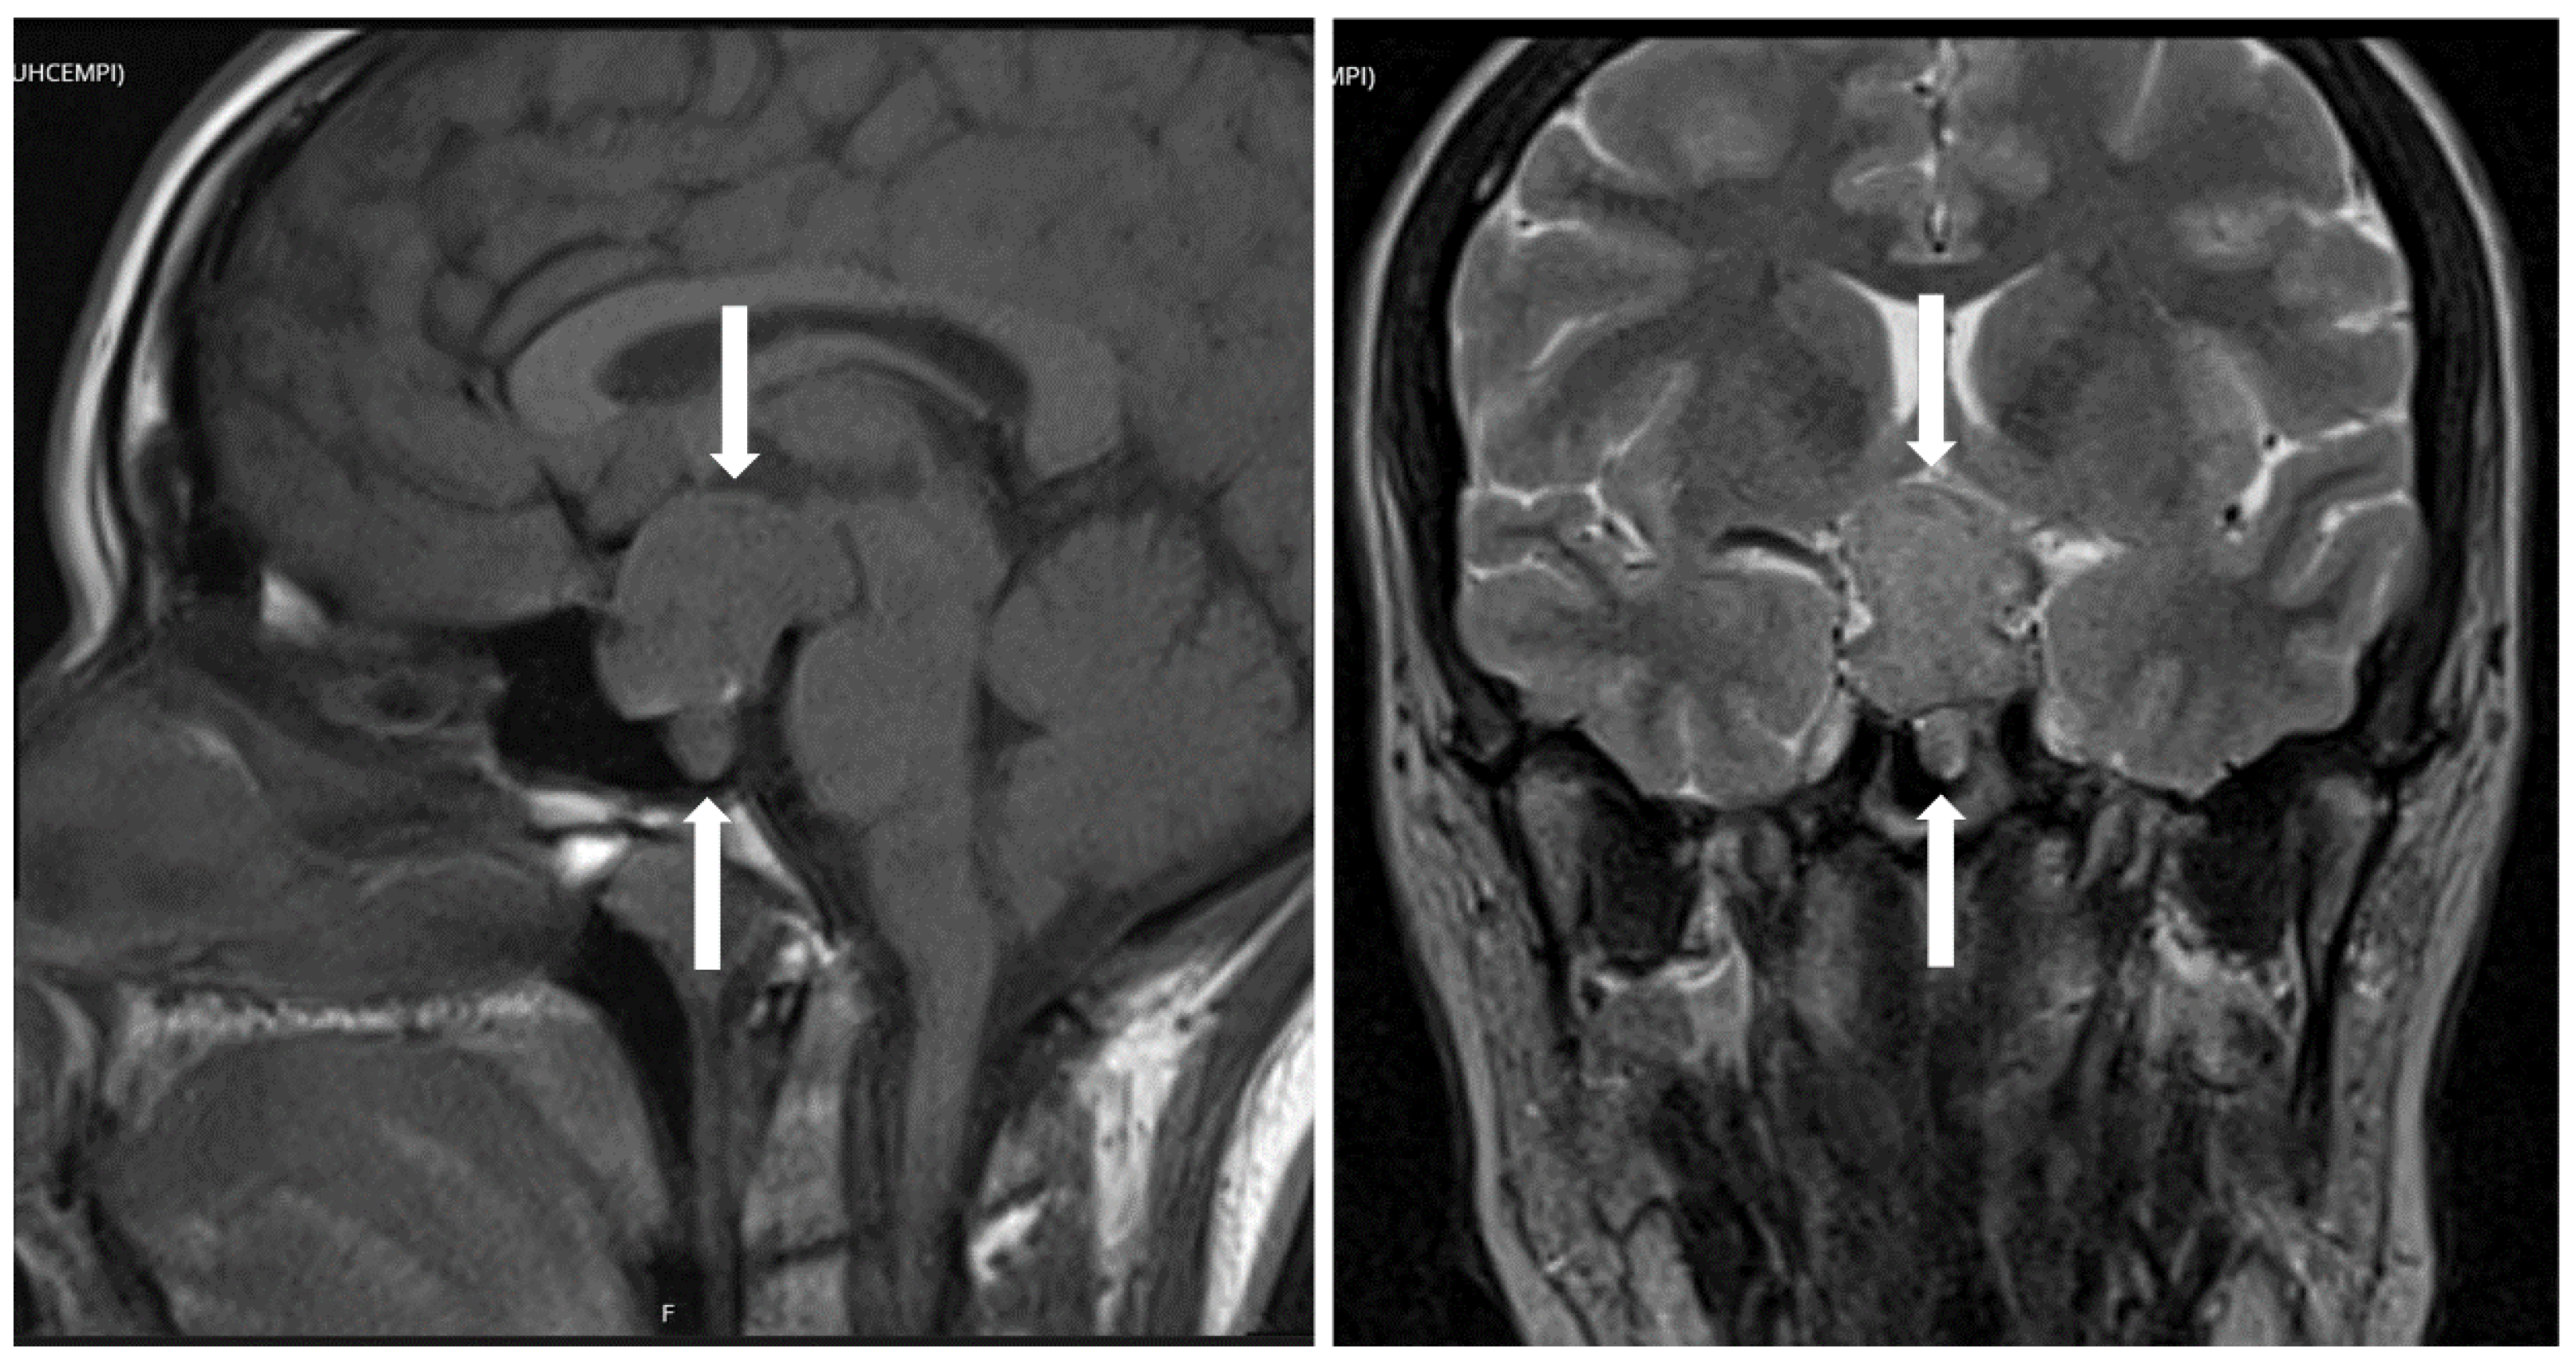

5. Hypothalamic Tumors

- Asa, S.L.; Mete, O. Hypothalamic Endocrine Tumors: An Update. J. Clin. Med. 2019, 8, 1741. [Google Scholar] [CrossRef]

- Asa, S.L.; Scheithauer, B.W.; Bilbao, J.M.; Horvath, E.; Ryan, N.; Kovacs, K.; Randall, R.V.; Laws, E.R.; Singer, W., Jr.; Linfoot, J.A.; et al. A case for hypothalamic acromegaly: A clinicopathological study of six patients with hypothalamic gangliocytomas producing growth hormone-releasing factor. J. Clin. Endocrinol. Metab. 1984, 58, 796–803. [Google Scholar] [CrossRef]

- Puchner, M.J.A.; Lüdecke, D.K.; Saeger, W.; Riedel, M.; Asa, S.L. Gangliocytomas of the sellar region—a review. Exper. Clin. Endocrinol. 1995, 103, 129–149. [Google Scholar] [CrossRef] [PubMed]

- Cossu, G.; Daniel, R.T.; Messerer, M. Gangliocytomas of the sellar region: A challenging diagnosis. Clin. Neurol. Neurosurg. 2016, 149, 122–135. [Google Scholar] [CrossRef] [PubMed]